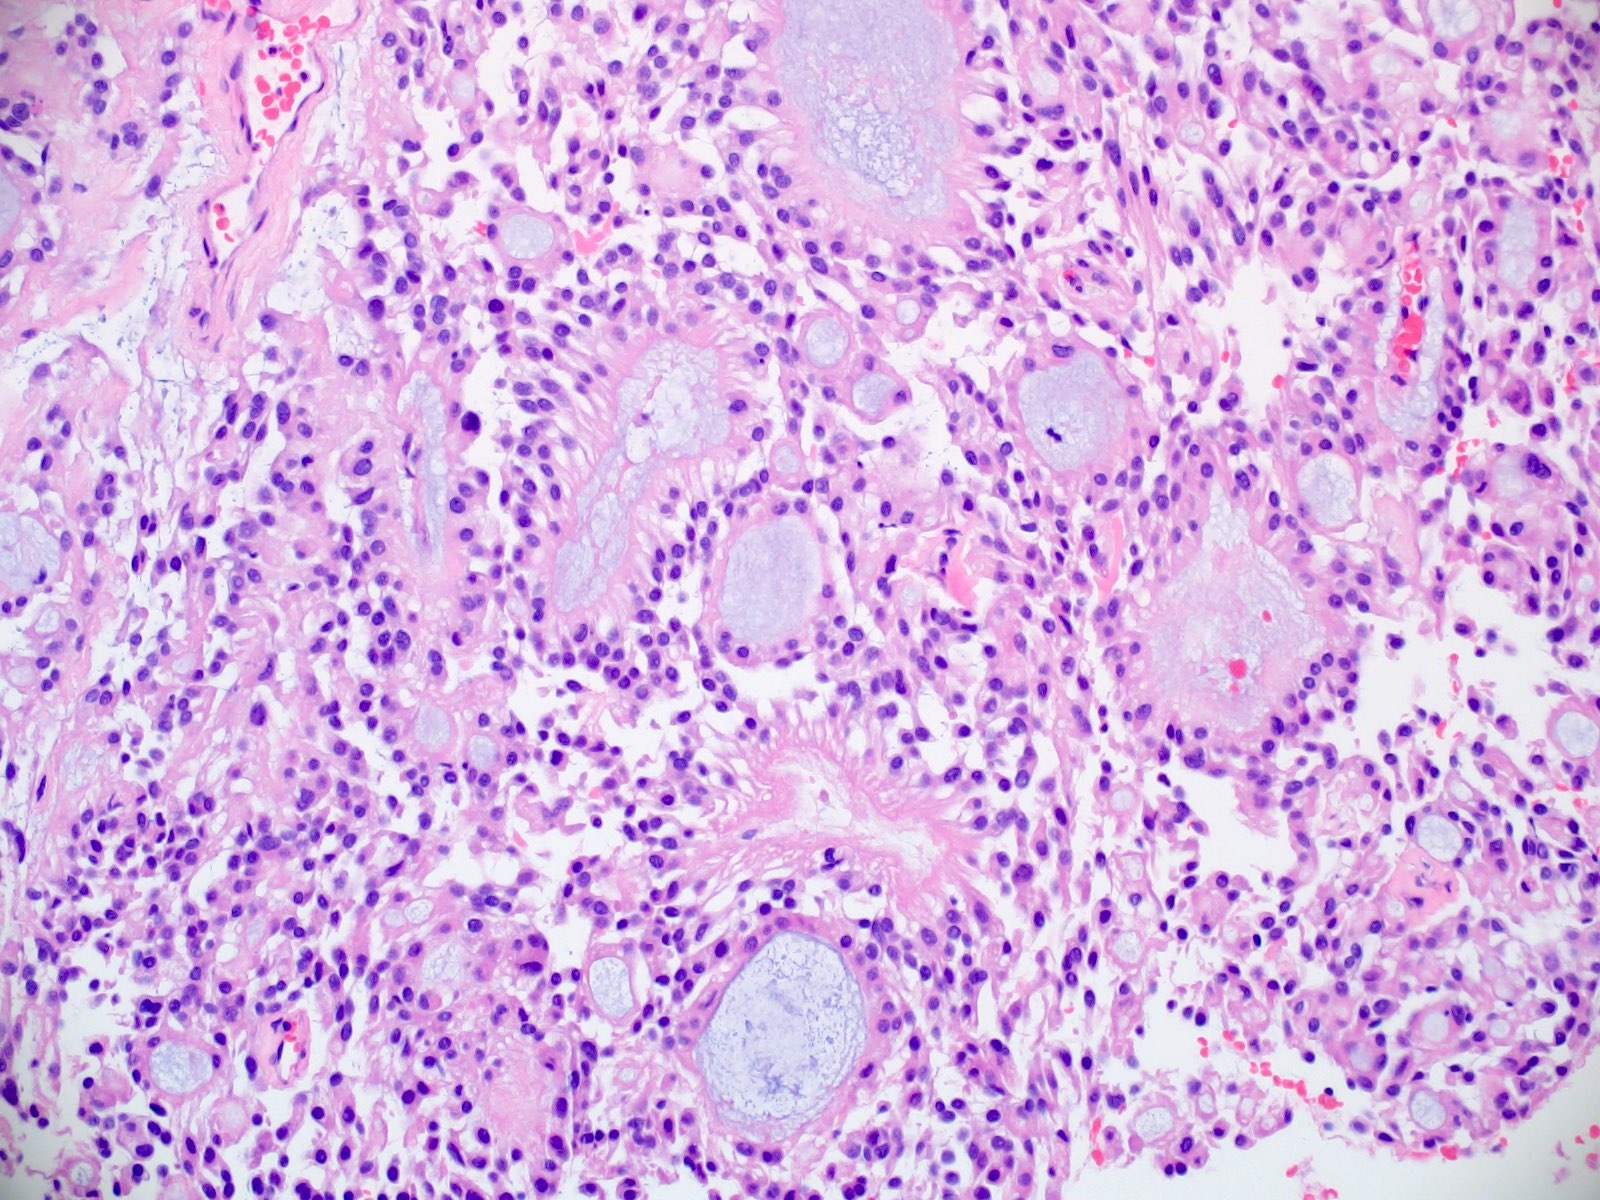

Microscopic (histologic) description

- Most common pattern is radial arrangement of cuboidal to epithelioid elongated glial tumor cells around hyalinized fibrovascular (central, often hyalinized blood vessels) cores in a papillary configuration

- Accumulation of basophilic myxoid material around blood vessels (myxoid stroma) and in microcysts

- Myxoid material is highlighted by PAS and Alcian blue positive staining

- In cases composed of confluent sheets of epithelioid cells with little or no papillary structures, PAS and Alcian blue positivity is useful in reaching a correct diagnosis

- Fascicular growth and spindle cells are common

- Pleomorphic tumor giant cells can be seen

- Occasionally tumor cells show distinctive eosinophilic balloons; these are PAS positive spherules that demonstrate spiculated reticulin staining (Am J Surg Pathol 1996;20:1091)

- Uncommon examples reported as anaplastic myxopapillary ependymomas show hypercellularity and reduced mucin in association with at least 2 of the following features: ≥ 5 mitoses / 10 high power field, Ki67 labeling index ≥ 10%, microvascular proliferation, spontaneous necrosis (Brain Pathol 2019;29:75)

Microscopic (histologic) images